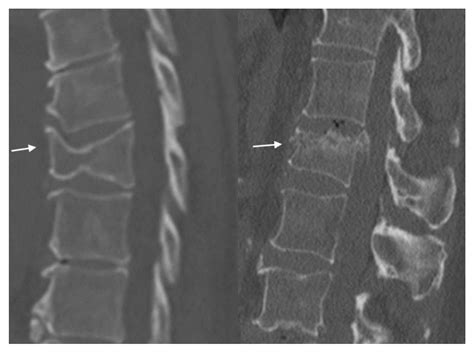

• Imaging Tests: X-rays are the primary tool for diagnosing fractures. In some cases, CT scans or MRIs may be used for more detailed images.

Imaging tests are crucial for understanding the acute fracture meaning and planning the appropriate treatment. X-rays provide clear images of the bone structure, helping to identify the type and severity of the fracture.